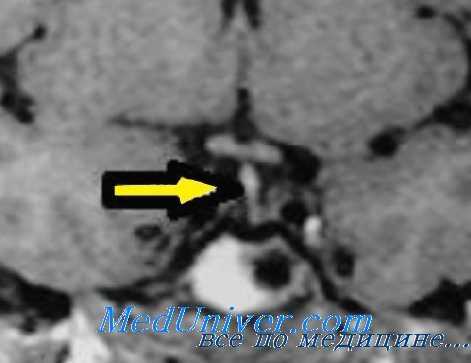

- Методы медицинской визуализации. Прицельный рентгенологический снимок турецкого седла позволяет выявить уменьшение размеров железы. Более подробную информацию о структуре и изменениях органа предоставляют томографические методики (МРТ, компьютерная томография).

- Нейровизуализация. Чтобы обнаружить органические поражения гипоталамо-гипофизарной зоны, проводится рентгенография турецкого седла, МРТ или КТ головного мозга. При необходимости обследование дополняется церебральной ангиографией, электроэнцефалографией.